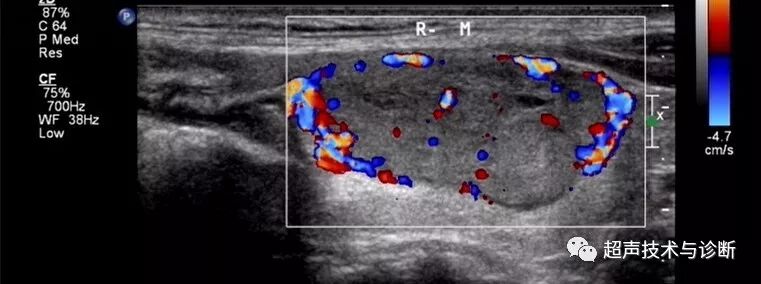

4 CDFI:结节周边声晕处可见环状包绕的血流信号,外周血流多于结节内部血流信号。

(图3-6)甲状腺滤泡型腺瘤,结节内部及周边均可见较丰富血流,周边可见环状血流信号